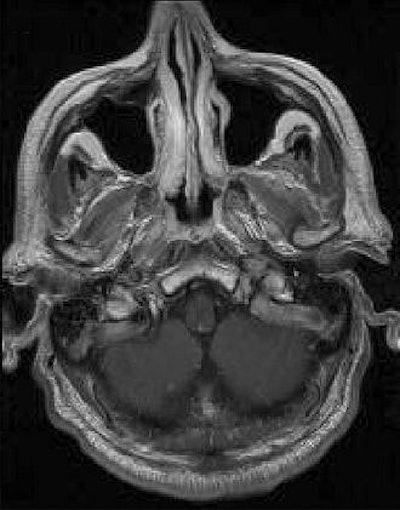

| Above, transverse T1-weighted SE MR image (590/12) in 61-year-old man with metastatic lung cancer after administration of 0.1 mmol/kg of gadopentetate reveals multiple enhancing lesions in right cerebellum and posterior medulla. Below, image acquired with identical parameters as previous image after administration of 0.1 mmol/kg of gadobenate reveals improved contrast enhancement of lesions seen with gadopentetate and unequivocal detection of two additional metastatic lesions (arrows) in right cerebellar hemisphere. |